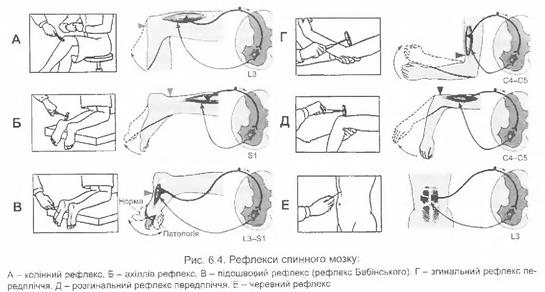

Фізіологія нервової системи

Соматична нервова система

Фізіологія нервової системи